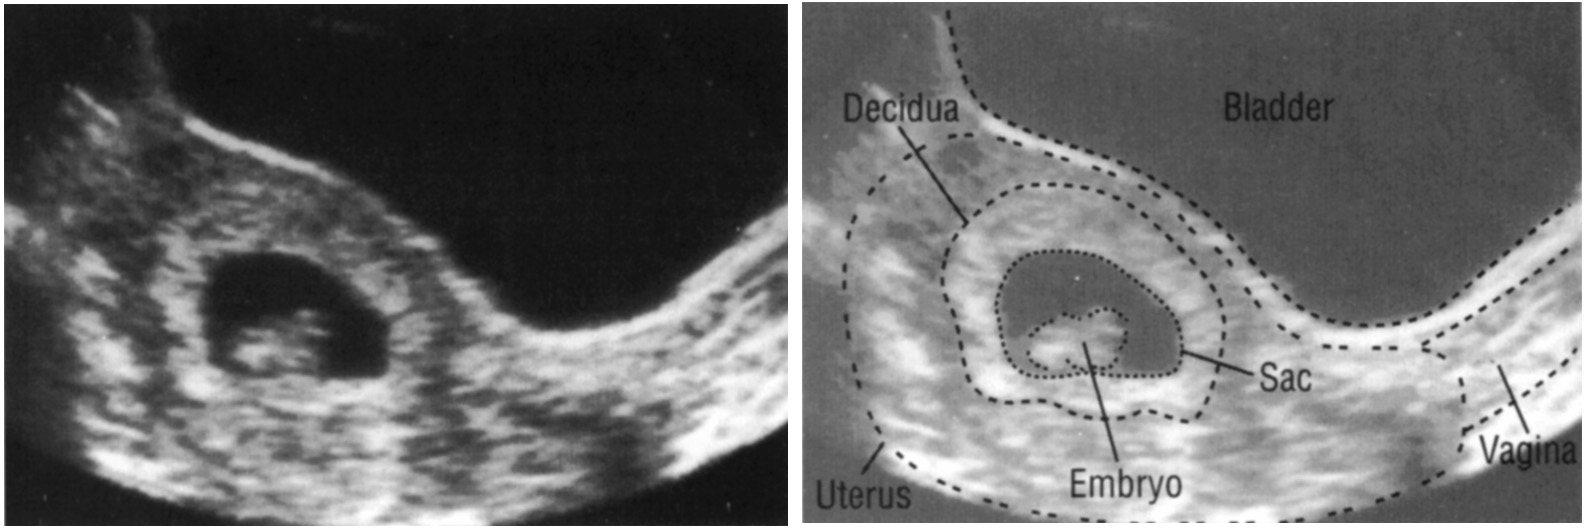

Внематочная беременность

Вероятной причиной того, что в ходе ультразвукового исследования беременной женщины на мониторе УЗ-сканера не виден зародыш, является эктопическая, или внематочная беременность. В этом случае закрепление и развитие плодного яйца происходит за пределами матки. Как правило, в такой ситуации его обнаруживают в фаллопиевых трубах. Однако не исключена вероятность его имплантации в брюшной полости, шейке матки, яичниках.

Помимо прекращения менструации и увеличения концентрации хорионического гонадотропина человека, на наличие данного патологического процесса указывает отсутствие плодного яйца в маточной полости. Во время УЗИ оно обнаруживается в области придатков или шейки матки в виде объемного образования. Если в ходе исследования визуализацию плодного яйца затрудняют его небольшие размеры и слабая слышимость работы сердца, на 7-й неделе увеличивающиеся в размерах плодные оболочки провоцируют деформацию окружающих тканей, что отчетливо видно при проведении диагностической процедуры.